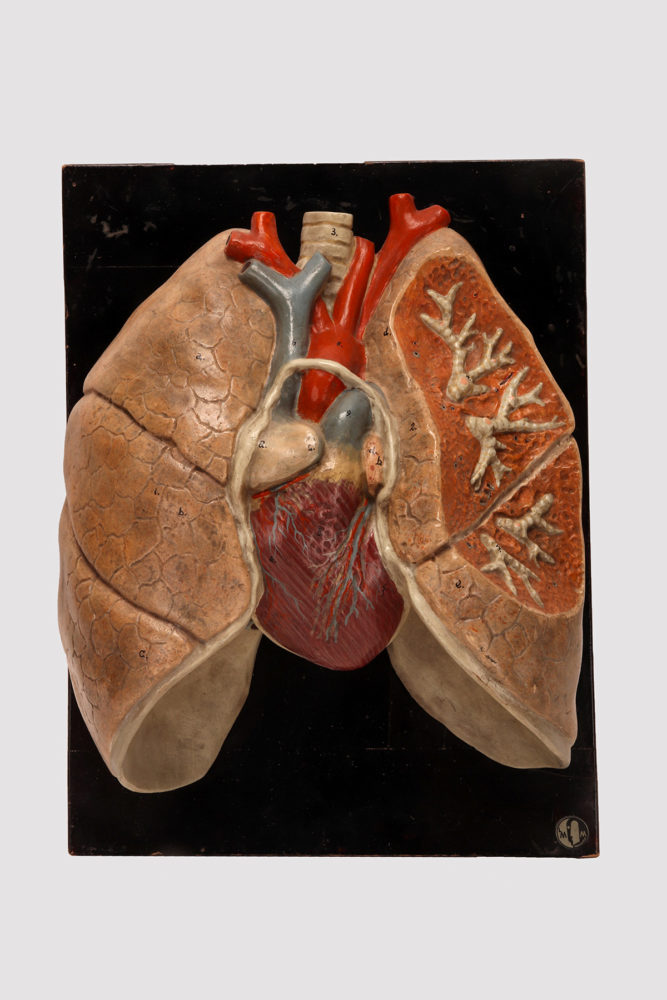

Anatomical model for class of the lungs and heart, Germany 1920.

Rare anatomical model for class, depicting human lungs and heart, made out of painted plaster, mounted on a black fruit wooden base. By Louis M. Meusel, Germany circa 1920.

13” – 33 CM H 9,75” – 25 CM L 5.75” – 15 CM D